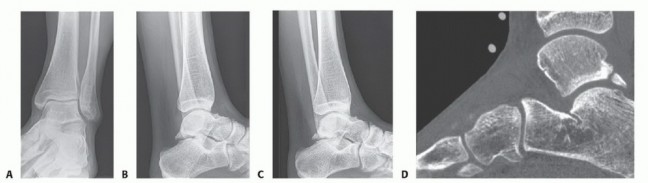

DEFINITION There are several reasons for cartilaginous defects of the ankle: Traumatic injury Osteochondritis…

DEFINITION Medium-sized osteochondral defects of the talar dome May approach the talar shoulder (transition o…